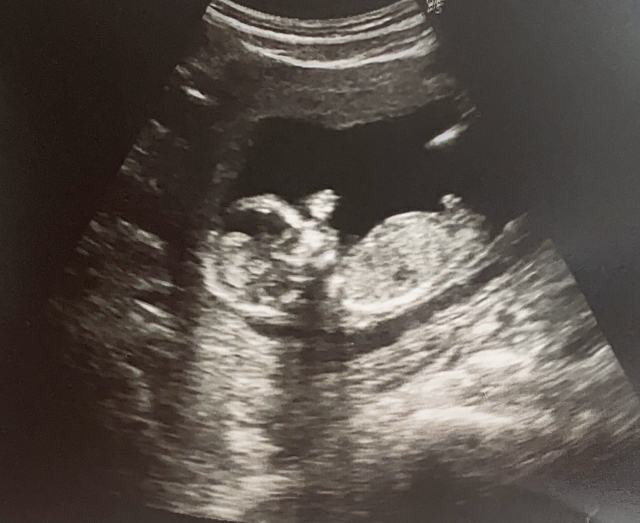

王樂明指出,第2個案例是20幾歲女性,第2次懷孕20週要終止妊娠,由於該病患月經不規則,也不知道懷孕,當她發現時胎兒已達20週,而她首次懷孕時也是終止掉,王樂明詢問對方「為何不做避孕措施?」病患則無任何回應,讓他不禁感嘆「對於這種事情如果在沒有足夠條件和準備之下生下小孩,傷害的也是小孩,或許終止妊娠對她是好的吧」。